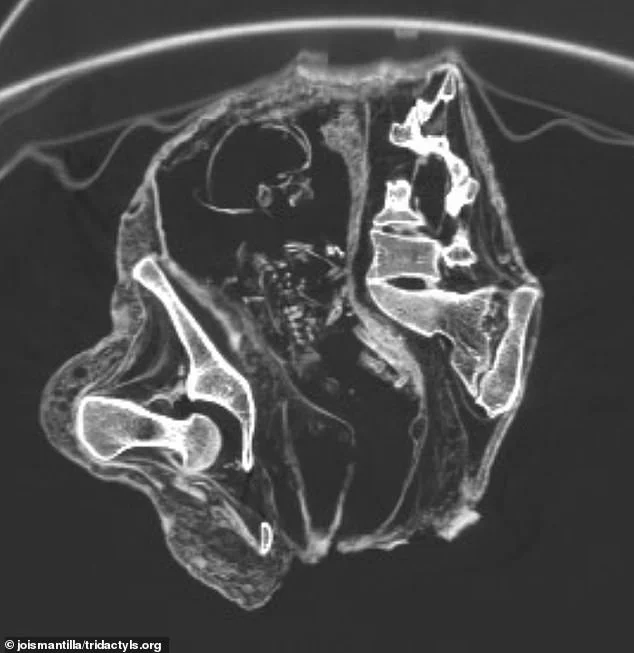

В случае с Монтсеррат (на фото) исследователи предположили, что причиной смерти стала серьезная травма, полученная в течение длительного периода времени.

Тайна, окружающая причудливые «инопланетные» мумии, найденные в Перу, углубилась после того, как ученые заявили, что обнаружили плод внутри утробы одного из «трупов». Компьютерная томография (на фото) зафиксировала плод, лежащий на спине.